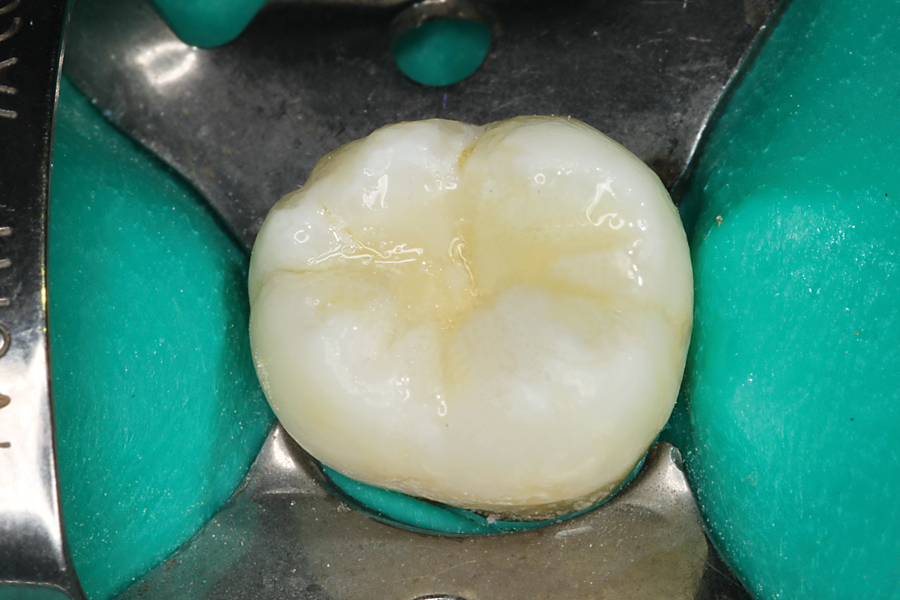

THE PERIMETER PREPARATION

The composite restoration is the basic foundation of the general dental practice. Countless composites are placed by dentists every day. Through the science of adhesive dentistry these restorations can be conservative and provide long term service. With time and function some breakdown may occur, usually at the margin of the restoration, the interface between tooth … Read more